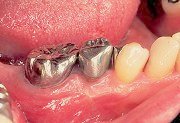

3

| ジーシーメンブレンは吸収性のた め、トリミングは試適膜で行っておく。トリミングは分岐部、根面を完全に被覆し、さらに周囲骨を3mm以上覆うことを確認しながら行う。 |

4

| 試適膜に合わせてジーシーメンブ レンをトリミングした状態。この時に、試適膜に血液等が付着しているとトリミング時にメンブレンが膨潤してしまうので注意が必要。 |